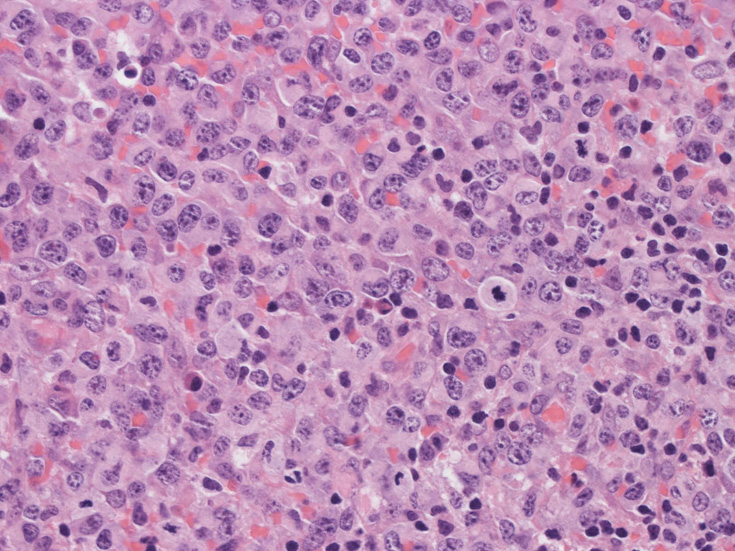

腹膜脂肪組織内から生検されたリンパ節は基本構造を失っている。低倍率のHE所見では異型細胞が不鮮明な結節構造を形成して増殖している。一次リンパ濾胞を腫瘍細胞が置換しているように見える所見がある。

高倍率x400では, 増殖細胞はcentroblastに似て複数の明瞭な核小体をもった淡明な大型類円ないし卵円形核を持っている。核分裂像が多い。この症例では多型はめだたない。典型的な腎臓型のくびれた核を持つ細胞などはない。ALKの形態的variant症例と考えられるが, 化学療法後の再発による影響も否定できない。